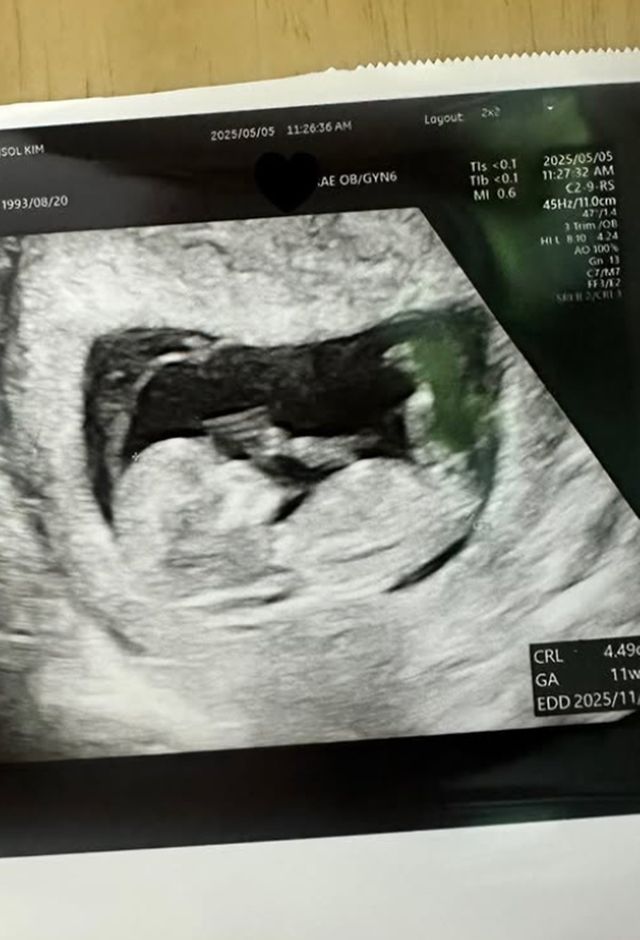

트루디는 9일 오후 자신의 SNS에 초음파 사진을 공유하며 “안녕하세요 트루디입니다. 행복한 가정의 달, 잘 보내고 계신가요. 지금도 믿기지 않지만, 제가 올해 11월에 엄마가 됩니다”라고 직접 임신 소식을 전했다.

트루디는 “태명은, 금똥이에요. 배가 너무 나와서.. 똥인줄 알았는데, 알고보니 금덩이라서요. 축하해 주신 모든분들 감사합니다”라며 “아직 많이 서툴지만, 많이 도와주세요-! 사랑해유”라는 말을 덧붙였다.